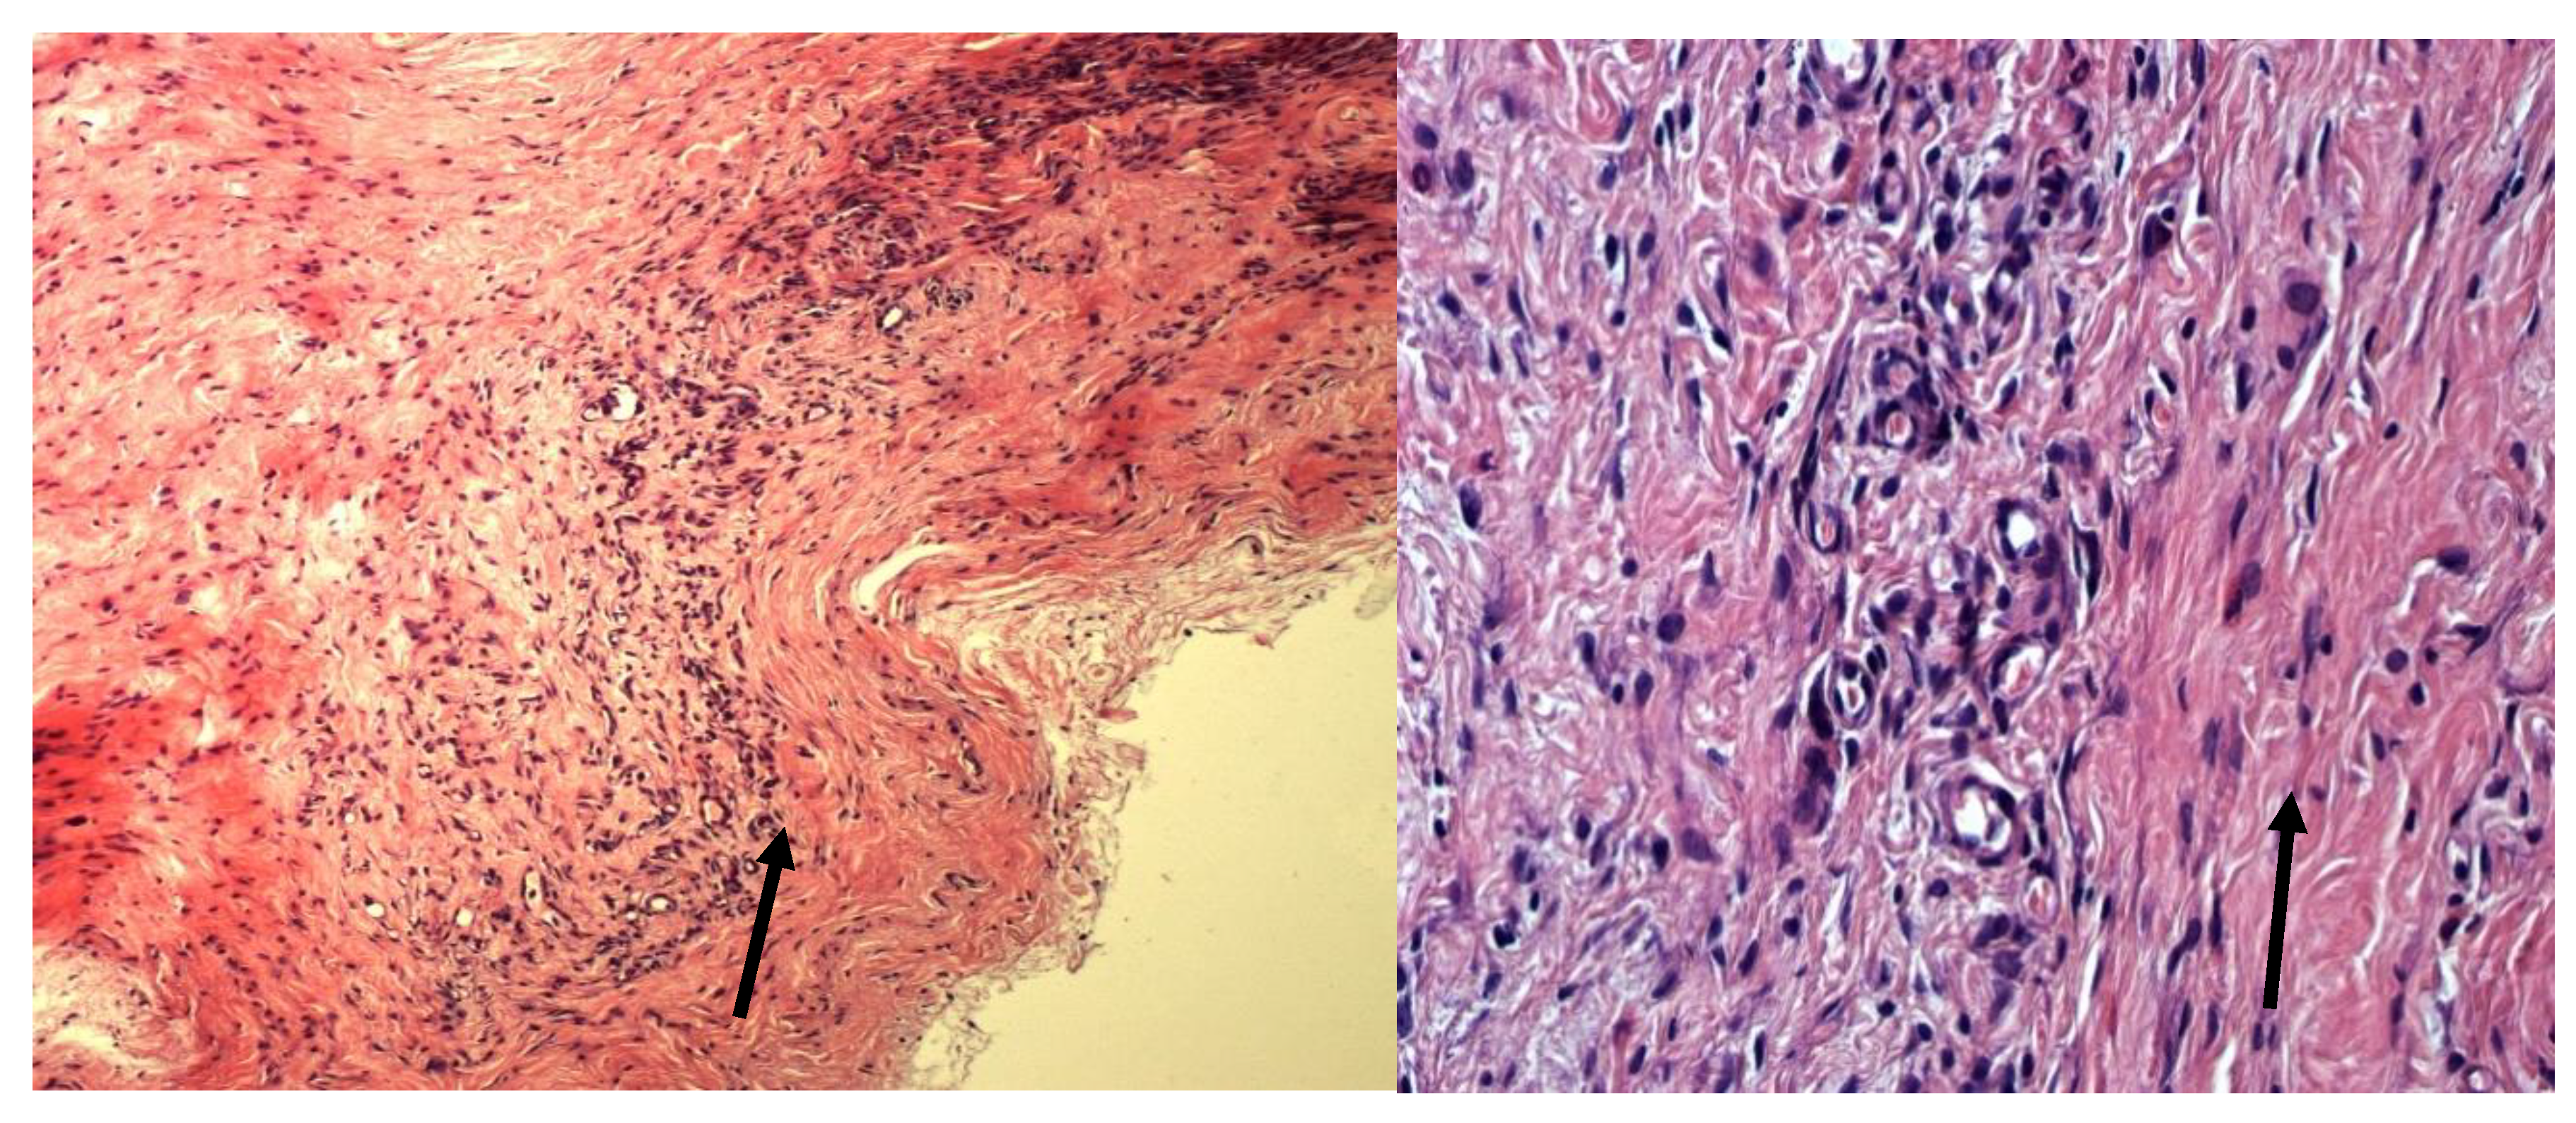

As a result of histological examination, we obtained convincing evidence of the different effects on the tissue around the implanted fragments of lyophilized amniotic membrane treated with glycerin (Group I) (Figure 1) and amniotic membrane fragments not treated with glycerin prior to lyophilization (Group II).

Lyophilized amniotic membrane on tissue slides from animals in Group I (the biomaterial was treated with glycerin before lyophilization) is clearly visible, its fibrous structure is preserved, and slight edema is noted. The surrounding tissues are slightly edematous and infiltrated with sporadic mast cells, macrophages, and fibroblasts. Isolated blood-filled vessels are present (Figure 1).

Figure 1. Histological preparation of the implantation zone of a fragment of lyophilized amniotic membrane treated with glycerin. Stained with hematoxylin and eosin. Magnification A—100x. B—400x. The arrow indicates the preserved amniotic membrane.

Group II specimens (biomaterial not treated with glycerin before lyophilization) demonstrate more pronounced lysis and replacement of lyophilized amniotic membrane, as well as macrophage infiltration. The surrounding tissues are infiltrated with a large number of mast cells. Numerous newly formed vessels are also observed.